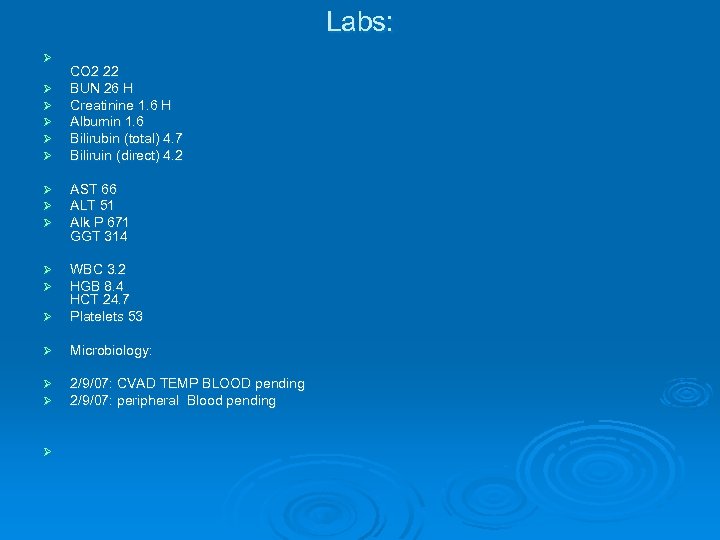

Labs: Ø Ø Ø CO 2 22 BUN 26 H Creatinine 1. 6 H Albumin 1. 6 Bilirubin (total) 4. 7 Biliruin (direct) 4. 2 Ø Ø Ø AST 66 ALT 51 Alk P 671 GGT 314 Ø Ø Ø WBC 3. 2 HGB 8. 4 HCT 24. 7 Platelets 53 Ø Microbiology: Ø Ø 2/9/07: CVAD TEMP BLOOD pending 2/9/07: peripheral Blood pending Ø